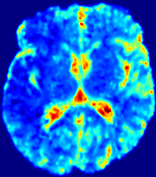

Slice #1Slice #2Slice #3Slice #4Slice #5Slice #6𝐕gt𝟐subscriptnormsuperscript𝐕gt2\|\bf{V}^{\text{gt}}\|_{2}Refer to captionRefer to captionRefer to captionRefer to captionRefer to captionRefer to caption𝐕est𝟐subscriptnormsuperscript𝐕est2\|\bf{V}^{\text{est}}\|_{2}Refer to captionRefer to captionRefer to captionRefer to captionRefer to captionRefer to captionRefer to caption1.51.51.51.21.21.20.90.90.90.60.60.60.30.30.30.00.00.0(mm/s)𝑚𝑚𝑠(mm/s)Destsuperscript𝐷estD^{\text{est}}Refer to captionRefer to captionRefer to captionRefer to captionRefer to captionRefer to captionRefer to caption0.0150.0150.0150.0120.0120.0120.0090.0090.0090.0060.0060.0060.0030.0030.0030.0000.0000.000(mm2/s)𝑚superscript𝑚2𝑠(mm^{2}/s)

Figure 14: PIANO identifiability testing: advection imaging via advection-diffusion. Top row shows 𝐕gt2subscriptnormsuperscript𝐕gt2\|{\bf{V}}^{\text{gt}}\|_{2} used for simulating ground truth pure advection. Rows below show the estimated 𝐕est2subscriptnormsuperscript𝐕est2\|{\bf{V}}^{\text{est}}\|_{2} and Destsuperscript𝐷estD^{\text{est}} on corresponding slices. Note that the plotted value scale for Destsuperscript𝐷estD^{\text{est}} is 0.01 of that for 𝐕gt2subscriptnormsuperscript𝐕gt2\|{\bf{V}}^{\text{gt}}\|_{2} and 𝐕est2subscriptnormsuperscript𝐕est2\|{\bf{V}}^{\text{est}}\|_{2}.

We use the same ‘Advection Imaging’ simulation of Sec. 4.2.1 as the concentration dataset for PIANO. However, instead of modeling pure advection (Eq. 15), we let PIANO estimate both velocity 𝐕estsuperscript𝐕est{\bf{V}}^{\text{est}} and diffusivity Destsuperscript𝐷estD^{\text{est}} via the advection-diffusion PDE (Eq. 2) underlying the proposed PIANO model. Fig. 14 shows the estimated 𝐕est2,subscriptnormsuperscript𝐕est2\|{\bf{V}}^{\text{est}}\|_{2}, and Destsuperscript𝐷estD^{\text{est}} fields for one patient. Although PIANO has the freedom to estimate both a velocity and a diffusivity field from pure advection, PIANO differentiates well between advection and diffusion: the estimated 𝐕est2subscriptnormsuperscript𝐕est2\|{\bf{V}}^{\text{est}}\|_{2} successfully reproduces the ground truth 𝐕gt2subscriptnormsuperscript𝐕gt2\|{\bf{V}}^{\text{gt}}\|_{2} governing the simulated advection process, just as it already did in the ‘Advection Imaging via Advection’ test (Fig. 12). More importantly, the estimated diffusivity Destsuperscript𝐷estD^{\text{est}} is orders of magnitudes smaller than 𝐕est2subscriptnormsuperscript𝐕est2\|{\bf{V}}^{\text{est}}\|_{2}, indicating the estimated diffusion is negligible compared to the estimated advection, which is highly consistent with the underlying pure advection of the simulated data.